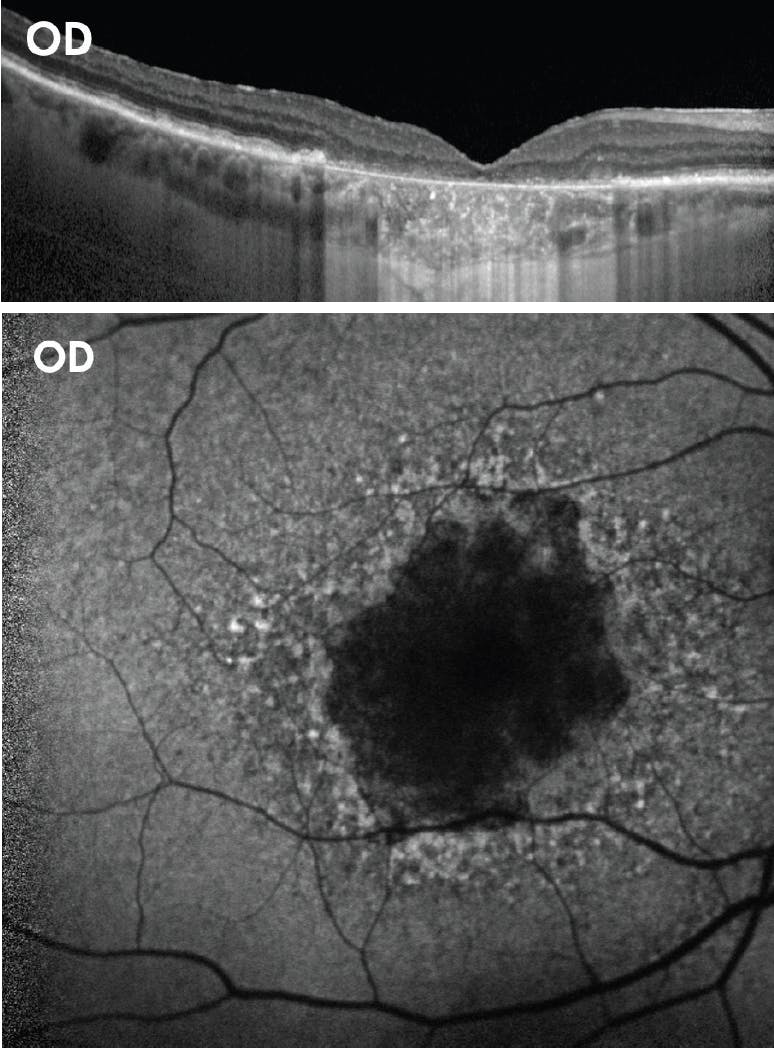

Figure 8. The right eye of a 74-year-old white male showed a hemorrhagic pigment epithelial detachment, choroidal neovascularization, and subretinal hemorrhage, as well as intraretinal fluid (A). After 2 years of anti-VEGF treatment for wet AMD, the right eye had developed extensive RPE scarring and atrophy (B). The patient’s left eye had drusen and a small area of atrophy just temporal to the fovea at presentation (C). After 2 years, the left eye showed GA growth temporal to the fovea (the white arrow points to a hypertransmission defect). (Case and images provided with permission by Roger A. Goldberg, MD, MBA).

After 2 years of treating the right eye with anti-VEGF for wet AMD, that eye developed extensive RPE scarring and atrophy secondary to wet AMD, and its vision declined to counting fingers. There was clearly GA growth just temporal to the fovea in the left eye, seen on both fundus autofluorescence and on OCT with an increased hypertransmission defect. Although the vision was still 20/30 in the left eye, the patient complained that the quality of the vision in that eye was declining. Thus, we elected to treat that left eye with SYFOVRE.

This case shows the difference in using OCT versus fundus autofluorescence to detect GA. I don’t think I would have appreciated how much atrophy was present in the left eye just by looking at its initial OCT, especially in light of its good vision.